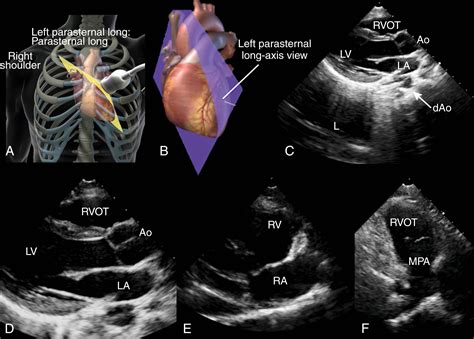

Obtaining a high-quality Parasternal Long Axis view requires a systematic approach. Here are the steps involved:

• Patient Positioning: The patient is typically positioned in the left lateral decubitus position, which allows for better access to the heart.

• Probe Placement: The ultrasound probe is placed in the parasternal position, just to the left of the sternum, in the third or fourth intercostal space.

• Orientation: The probe is oriented to capture a longitudinal section of the heart, with the marker pointing towards the patient's right shoulder.

• Image Optimization: The depth, gain, and focus of the ultrasound machine are adjusted to optimize the image quality. The sector width is narrowed to enhance resolution.